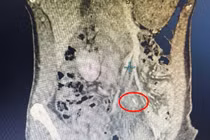

di-vat.jpg

Xương cá được lấy ra an toàn - Ảnh BVCC

Bệnh nhân N.N.T. (40 tuổi, ngụ Vĩnh Long) nhập viện trong tình trạng đau âm ỉ vùng hạ vị suốt 4–5 ngày, cơn đau tăng lên khi di chuyển. Trước đó, bệnh nhân đã đi khám tại một phòng khám tư.

Qua siêu âm, bác sĩ nghi ngờ có dị vật tại thành bụng gây hình thành ổ áp xe nên khuyến cáo bệnh nhân đến cơ sở chuyên khoa để kiểm tra thêm.